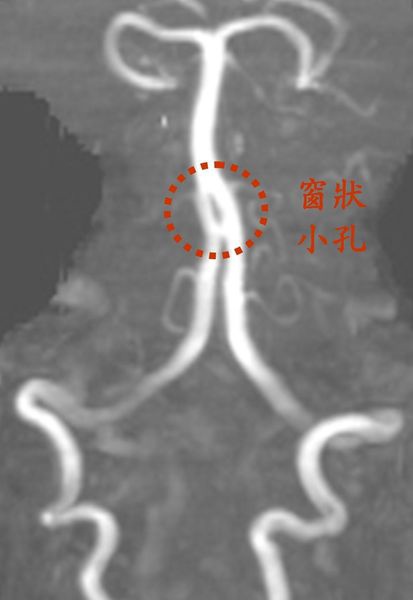

一名五十六歲女性,反覆發作暈眩已經長達十多年,只要運動或壓力大時也會引起頭暈,而轉頭、洗澡也會引發暈眩,這暈眩每次都發作都會持續大約半小時到一小時。血管磁振造影顯示基底動脈上有一個環型血管結構,當他在做某些動作時,使腦幹和小腦的供血出現不穩,造成暈眩。這種「窗型小孔」其實一種先天胚胎發育所遺留下來的痕跡,最常見於基底動脈,戲謔地說是腦袋裡有「洞」真的是一點也不為過。原本這先天性的血管異常並不會有症狀,通常不具臨床意義,可能是隨著年紀漸漸增加,血管的對外在刺激調節能力變差,開始會在患者姿勢改變時,腦部血流出現不穩,繼而引發。